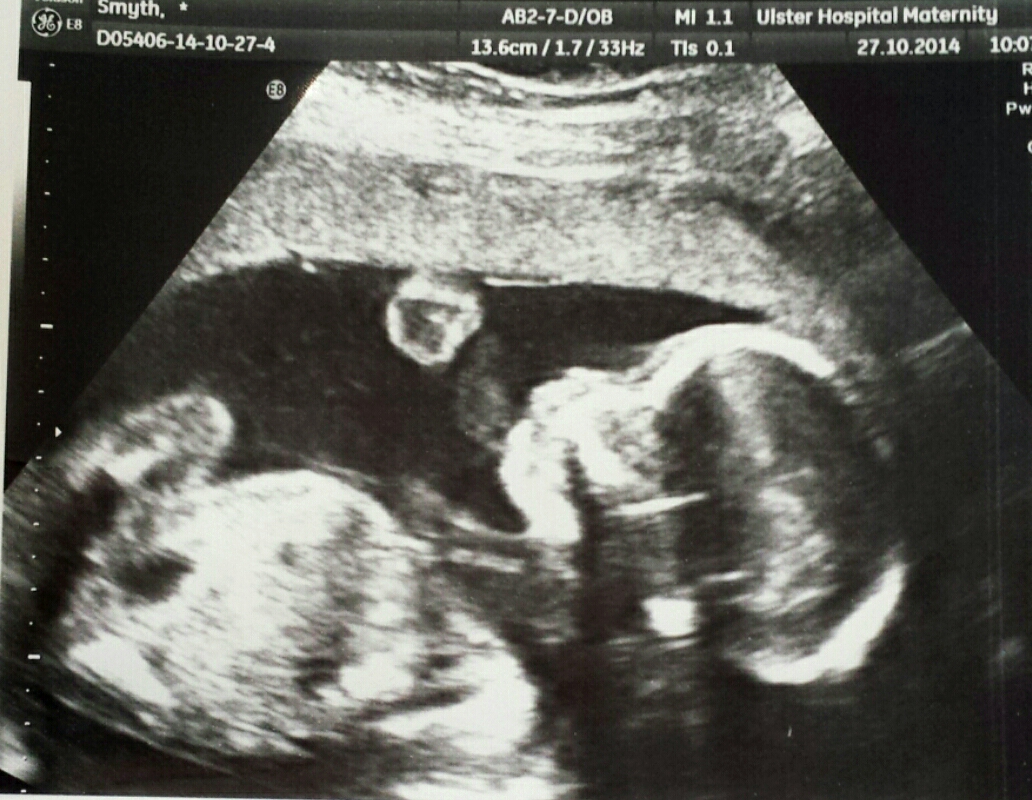

How Many Weeks Can You Tell The Gender Of Baby - Take it once, for fun, then take it as many times as you can to get all the different answers possible.. Which gender predictor is pure myth and which is based in science? In most cases, it will be an ultrasound that you will undergo between 18 and 20 weeks. An ultrasound is the most common way to determine a baby's gender. You can sometimes tell the gender via ultra sound. Be unique, be you, and remember, no matter what gender, we all live this life together.

In most cases, it will be an ultrasound that you will undergo between 18 and 20 weeks. The nipt (non invasive prenatal test) can determine as early as 10 weeks gestation the gender of the fetus. How many delta skymiles for a flight. Which gender predictor is pure myth and which is based in science? But, of course, many little babies are not accommodating and don't let the sonographer have a good but let me tell you, i had severe morning sickness with both my girls. Yet few studies, until now, have scrutinised how well they perform. Most people do, as soon as it is possible. The answer is simple, i.e how babygram can offer the most reliable baby gender prediction online.

The provider performing the ultrasound can usually tell the patient the gender of the baby. The gender of the baby is determined at conception, although differentiation of the sexual organs does not begin until the middle of the sixth week of chorionic villus sampling is generally performed at the end of the first trimester, as early as 10 weeks but more often between weeks 10 and 12 after your. Also how soon can one find out if she's carrying more than one child? Speak to your sonographer or midwife to find. How early can gender be determined by ultrasound? Some people claim male cats are friendlier and more outgoing than females. Early gender dna tests at 8 weeks. It takes 40 weeks for a baby to grow in a womb but if u deliver ur baby before 32 weeks then more likely u r going to have a premature baby i was pregnant and i carried my baby for 38 weeks i had a little boy he was 5lbs and. How can you learn your baby's sex? Yet few studies, until now, have scrutinised how well they perform. Traditional ultrasounds work by sending high frequency sound waves into. A sure way is amniocentesis. How many weeks can ultra sound tell baby gender?